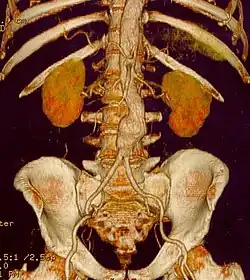

Abdominal aortic aneurysm

Abdominal aortic aneurysms (AAAs) are more common than their thoracic counterpart. One reason for this is that elastin, the principal load-bearing protein present in the wall of the aorta, is reduced in the abdominal aorta as compared to the thoracic aorta. Another is that the abdominal aorta does not possess vasa vasorum, the nutrient-supplying blood vessels within the wall of the aorta. Most AAA are true aneurysms that involve all three layers (tunica intima, tunica media and tunica adventitia). The prevalence of AAAs increases with age, with an average age of 65–70 at the time of diagnosis. AAAs have been attributed to atherosclerosis, though other factors are involved in their formation.[8] Risk factors for AAA include the male gender, aging, a history of smoking, hypercholesterolemia, and hypertension.[4][8][11] Reviews reported estimates for prevalence rates of AAA were 0.9-9% in men and 1–2% in women, where, generally, the incidence of AAA is four times greater in men compared to women at the same age.[4][8]

The risk of rupture of an AAA is related to its diameter; once the aneurysm reaches about 5 cm, the yearly risk of rupture may exceed the risks of surgical repair for an average-risk patient. Rupture risk is also related to shape; so-called "fusiform" (long) aneurysms are considered less rupture-prone than "saccular" (shorter, bulbous) aneurysms, the latter having more wall tension in a particular location in the aneurysm wall.[12]

Before rupture, an AAA may present as a large, pulsatile mass above the belly button. A bruit may be heard from the turbulent flow in the aneurysm. Rupture may be the first sign of AAA. Once an aneurysm has ruptured, it presents with classic symptoms of abdominal pain, which is severe, constant, and radiating to the back.[8]

The diagnosis of an abdominal aortic aneurysm can be confirmed by the use of ultrasound. Rupture may be indicated by the presence of free fluid in the abdomen. A contrast-enhanced abdominal CT scan is the best test to diagnose an AAA and guide treatment options.[14]